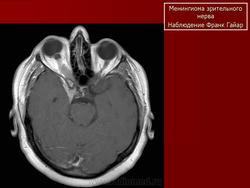

КТ-семиотика

На КТ срезах без контрастного усиления менингиома зрительного нерва выглядит изоденсной. Типично наличие линейных или точечных обызвествлений. Симптом «трамвайных рельс» отражает накопление КВ по сторонам гиподенсного зрительного нерва или наличие обызвествлений в структуре опухоли. Как правило, наиболее дистальная часть зрительного нерва, в месте его вхождения в глазное яблоко, не содержит обызвествлений.

При исследовании необходимо определить расположение бляшковидной менингиомы относительно бугорка турецкого седла и пластинки клиновидной кости, так как данный тип опухоли может распространяться интракраниально через канал зрительного нерва. КТ не позволяет адекватно визуализировать интракраниальное распространение опухоли, которое может привести к развитию двусторонней слепоты.